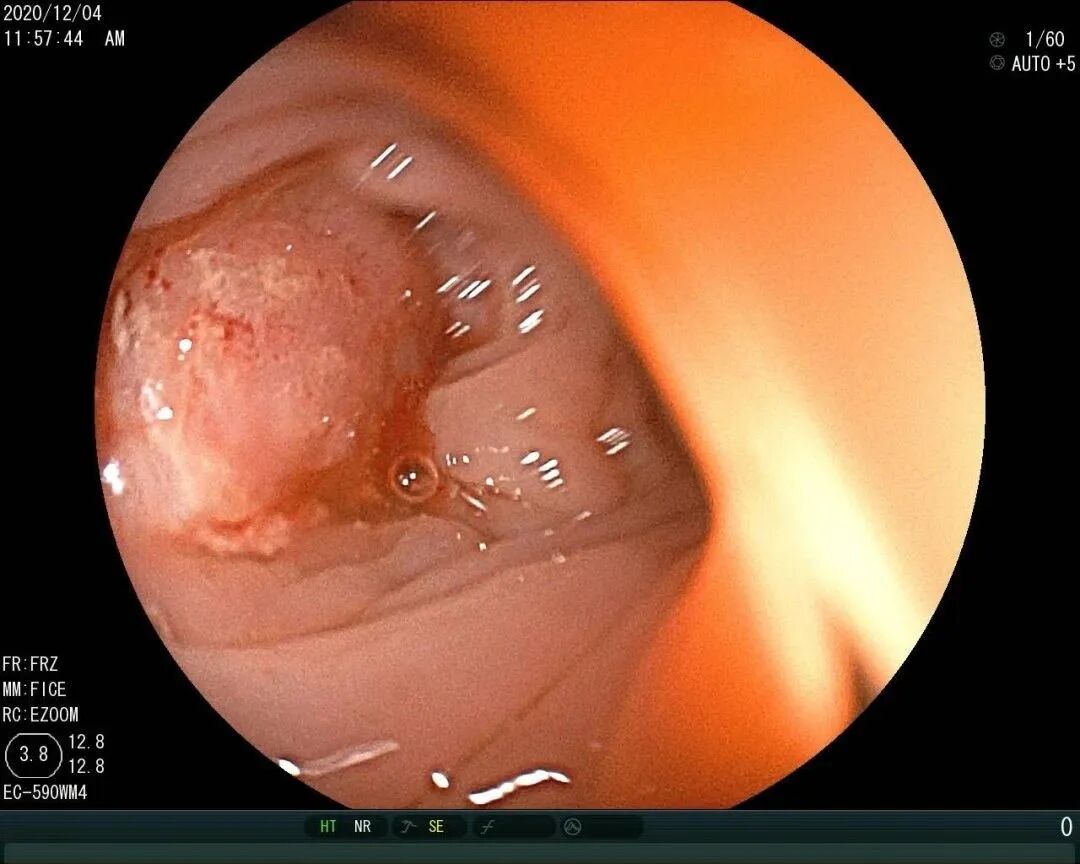

在全球,结直肠癌是发病率位居第三位、病死率位居第二位的肿瘤。肠镜筛查的普及以及手术方式的提升显著降低了结直肠癌的死亡率,但仍有一部分患者在初诊时已发展为晚期,失去手术根治的机会,且预后较差,5年生存率仅12%。许多转移性结直肠癌(mCRC)患者在经历一线治疗后,面临无药可用的困境。近年来,随着靶免联合治疗在系统治疗中逐渐前移,各种靶向治疗药物在mCRC的诊疗中也越发举足轻重。本文分享2例晚期结肠癌患者的诊疗经过,呈现瑞戈非尼在二线治疗为患者带来长生存的治疗价值及其良好的后线应用前景,以期为临床医生提供诊疗借鉴。 病例提供:海军军医大学附属长征医院 王湛 王湛 病例基本情况 一般信息:女 ,58岁。2020年10月,患者无明显诱因出现腹胀,无伴随症状,未予重视。后腹胀进行性加重,2020年11月中旬下腹部隐痛,与进食及体位变化无关,无肩背部放射痛。 辅助检查: 腹部超声:腹腔积液。 腹水脱落细胞病理:腺癌。 腹部增强CT:结肠肝曲癌;腹盆腔积液,腹盆腔腹膜多发转移。 结肠镜(2020-12-4):升结肠近肝曲见隆起型新生物,范围约4cm,新生物表面分叶状,质脆,触之易出血。肠腔狭窄,内镜尚可通过。 2020-12-8病理:横结肠,中分化腺癌,含部分粘液腺癌。 一线治疗2020-12-03至2021-02-24 CAPEOX+贝伐珠单抗 治疗4周期 病情进展,腹胀、腹痛加重,腹水增加。 2021-3-31 PET-CT:腹腔内及腹膜、脾脏、纵隔及右侧心膈角区、左侧锁骨区多发代谢增高灶,结合病史,考虑转移;双肺转移;腹腔及盆腔积液;结肠显示欠清,请结合肠镜检查;双侧胸腔少量积液,左肺下叶部分不张;双肺少许慢性炎症;右肝血管瘤;左肾结石。;子宫术后,痔疮可能;脊柱退变,腰3不稳,腰3/4、4/5、腰5/骶1椎间盘突出。 PFS:3个月 2021-4-6,完善基因检测(腹水标本):KRAS/APC/TERT/TP53/ target=_blank class=infotextkey>P53 突变,TMB 7.98/Mb,MSS 二线治疗,2021-04-02至2021-12 2021-3-31 2021-6-2 2021-8-6肠镜:结肠镜顺利插至回盲部,回盲瓣呈唇状。结直肠粘膜呈桔红色,光滑湿润,有光泽。血管纹理呈树枝状,清晰可见。 PFS:8月 三线治疗,2021-12-13至2022-01-23 三氧化二砷 2021-6-2 2021-11-22 2021-11-22 2022-2-8 PFS:2月 四线治疗,2022-02-10 化疗+免疫+瑞戈非尼+三氧化二砷 2022-2-10开始使用小剂量化疗(雷替曲塞+奥沙利铂+伊立替康)+免疫(信迪利单抗)+瑞戈非尼+三氧化二砷治疗。 疗效评估(2022-9-20):患者病情再次取得缓解。 2022-9-22至今采用维持治疗,降低治疗强度:雷替曲塞 +信迪利单抗+瑞戈非尼+三氧化二砷 2022-9-20 2023-2-8 PFS:13个月+ 该患者为中年女性,诊断为晚期多发转移性结肠癌,基因检测提示KRAS突变,BRAF、NRAS野生型,微卫星稳定,无法进行根治性切除。一线治疗加予CAPEOX联合贝伐珠单抗,治疗4周期后出现病情进展,腹胀、腹痛加重,腹腔积液增加,二线采用瑞戈非尼联合免疫和化疗,患者耐受良好,1周期后腹胀明显缓解,全身状态、PET-CT、肠镜结果较之前明显改善,继续原方案治疗,PFS长达8月。二线治疗进展后完善基因检测,发现TP53 突变,经与患者充分沟通,三线治疗采用三氧化二砷,疗效不佳。四线治疗在三氧化二砷基础上加用瑞戈非尼+免疫+化疗,患者病情再次取得缓解,PFS 超过13个月。近年来,随着精准医学及靶向、免疫治疗的发展,mCRC的管理与治疗策略的制定也变得复杂,合理选择治疗手段、优化全程管理至关重要。本例患者经历了一线化疗联合免疫治疗后疾病出现快速进展,我们个体化地在二线治疗中应用瑞戈非尼联合方案,患者疾病得到控制,PFS 8个月。在四线治疗方案中,再次挑战瑞戈非尼,依然获得较好的疾病控制效果,目前PFS已超过13个月。基于CORRECT和CONCUR研究,瑞戈非尼用于mCRC三线治疗已积累大量临床数据,目前已成为mCRC三线标准治疗方案。此外,REGONIVO、REGOTORI以及RIN方案证实了瑞戈非尼联合免疫治疗MSS型肠癌取得更长的总生存期。一线治疗后疾病进展,能否将瑞戈非尼使用前移,在二线治疗中加用以进一步延长患者生存,以及前线已经暴露过瑞戈非尼,后线再次使用瑞戈非尼是否可行,仍待在临床研究中进一步证实。 02 病例分享二 病例提供:海军军医大学第一附属医院 王薇 王薇 病例基本情况 一般信息:男性,41岁。2020年10月8日,无明显诱因下出现便血,为鲜红色,伴肛门坠胀不适,无排便习惯改变,无腹胀,无消瘦。1997年因“胃溃疡”行胃部幽门切除术;2019年行混合痔手术。 辅助检查: CEA 3.4ng/ml,CA199 3.52u/ml。 当地医院肠镜(2020-11-20):(距肛缘8-10cm)可见粘膜不规则隆起,表面溃烂,易出血。 肠镜活检病理:(直肠)中分化腺癌。 盆腔MRI增强(2020-11-26):直肠中段癌,考虑mrT3N1Mx,MRF-,EMVI-。 肝脏MRI增强(2020-11-27):未见明显异常。 治疗经过 首次手术治疗2020-12-09 腹腔镜辅助直肠癌拖出式适形切除术+末端回肠造口术 术中探查:直肠下段肿物,质硬,未浸润浆膜层,周围系膜未见肿大淋巴结。肿瘤大小约4*4*2cm,占肠腔1/2周,系膜完整。 术后病理: 直肠溃疡型肿瘤大小4.5x3.5x1.5cm;中至低分化腺癌,部分为粘膜腺癌;浸润至外膜层; 癌结节( 3枚+)、脉管癌栓(+)、神经侵犯(+)、肿瘤出芽(+,PDC1级);上下切缘(-)、环周切缘(-)、吻合圈(-);周围淋巴结(2/6),直肠外膜淋巴结(2/4),最高群淋巴结(0/4); 基因分型:KRAS Exon-2 G12D突变,NRAS、BRAF、PIK3野生型;免疫组化:MSH2(+),MSH6(+),MLH1 (+),PMS2(+),pMMR;Ki-67 80%。 术后分期:pT3N2aMx IIIB期 术后辅助治疗(XELOX方案) XELOX方案化疗3周期; 拟行盆腔放疗50gy/25次,2021-03-25起放疗6次 术后复查 肝脏MRI增强(2021-03-27):肝脏多发结节,较前为新发,考虑肝内多发转移瘤 一线治疗,2021-04-22至2021-06-24 mXELIRI+贝伐珠单抗 治疗4周期 患者治疗后出现恶心呕吐,胃纳明显减退,Ⅱ°粒细胞下降,腹泻,脱发,轻度手足皮肤反应,手足冰凉,心悸。患者无法耐受继续治疗 维持治疗,2021-7-15至2021-8-26,卡培他滨+贝伐珠单抗,共计治疗3周期 肝脏MRI增强(2021-5-31、2021-8-24):肝右后叶上段7mm小结节灶,转移不除外,腹膜后稍大淋巴结较前相仿,随访。 2021-3-27与2021-5-31的肝脏MRI增强对比图 2021-8-24 肝脏MRI增强 盆腔MRI增强(2021-8-25):术区及骶前软组织肿胀,左侧条索影,结合CT考虑术区置管术后改变,较2021-06-01片大致相仿。 疗效评估:PR 后患者诉心悸、乏力、胃纳不佳;血压正常;心肌酶正常;心脏彩超LVEF 64%;EKG: 窦性心率,T波低平;尿蛋白(-)。患者对化疗非常抗拒。 二线治疗,2021-09-17至2021-12-15 盆腔MRI增强(2022-9-13):术区及骶前软组织肿胀,左侧条索影,结合CT考虑术区置管术后改变,较前片大致相仿。 胸部CT(2022-9-13): 右肺下小结节,随访。 疗效评估:PR。 2022-12-20肝脏MRI增强:平扫+增强未见明显异常。 2022-12-21盆腔MRI增强:直肠癌术后,盆腔区未见明显复发及转移病灶。 病例总结 该患者为中年男性,诊断为局部晚期直肠癌,原发灶术后分期IIIB期,基因检测KRASExon-2G12D突变、微卫星稳定。术后仅3月余在XELOX方案辅助化疗、盆腔放疗期间出现多发肝转移,疾病进展转移灶不可切除,进而接受XELIRI方案联合贝伐珠单抗二线全身治疗。治疗后肝脏多发转移瘤退缩理想,病灶明显缩小减少。但患者治疗副反应不可耐受,改卡培他滨联合贝伐单抗治疗后持续有效,但仍无法耐受副反应。遂予以瑞戈非尼靶向治疗:120mg日剂量口服,服用三周停用一周至今。患者耐受良好,近期复查未发现明显复发转移病灶。目前二线PFS已达23个月,瑞戈非尼二线维持治疗DoR17个月。目前,二线治疗在不同患者亚群的优选方案仍存在争议。而整个系统治疗到了三线阶段,标准治疗主要价值是能够延长患者的疾病控制时间,缩瘤效果和客观缓解率均不理想,并没有满足目前的治疗需求。根据目前的药物机制和临床研究结果,考虑到患者的具体情况:涵盖治疗目标、体质状况、对预估的不良事件的耐受性及是否存在相关危险因素、既往治疗用药情况等方面,我们采用了个体化的瑞戈非尼二线维持治疗方案取得良好疗效,这种治疗策略希望能在规范临床研究中证实。病例分享一